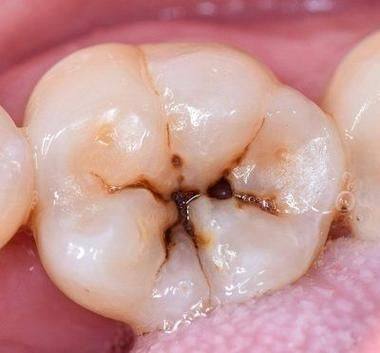

手术治疗之充填法

充填是治疗儿童龋齿的主要手术方法。要是想知道儿童龋齿怎么处理更好,特别多时候充填能起到良好的成效。治疗时,医生会先把龋坏的部分完全去除,接着制备合适的洞型,再对牙齿进行清洗和消毒,末尾用牙科材料把洞填充起来。这样做不仅能修复牙齿的外形,还能防止龋坏继续发展。

不同龋坏程度在充填治疗上也有差异。前龋时进行填充,成效是更好的;中龋进行填充,成效次之;如果是深龋,医生会尽量去除深部的龋坏组织,然后进行护髓、垫底充填。要是在去除龋坏组织的时候已经暴露了牙龈,而且孩子刺激痛症状比较明显,就需要先做牙髓治疗,之后再进行填充;要是去腐露髓孔小,但是刺激痛症状特别剧烈,就可以做直接盖髓后,再进行垫底填充。